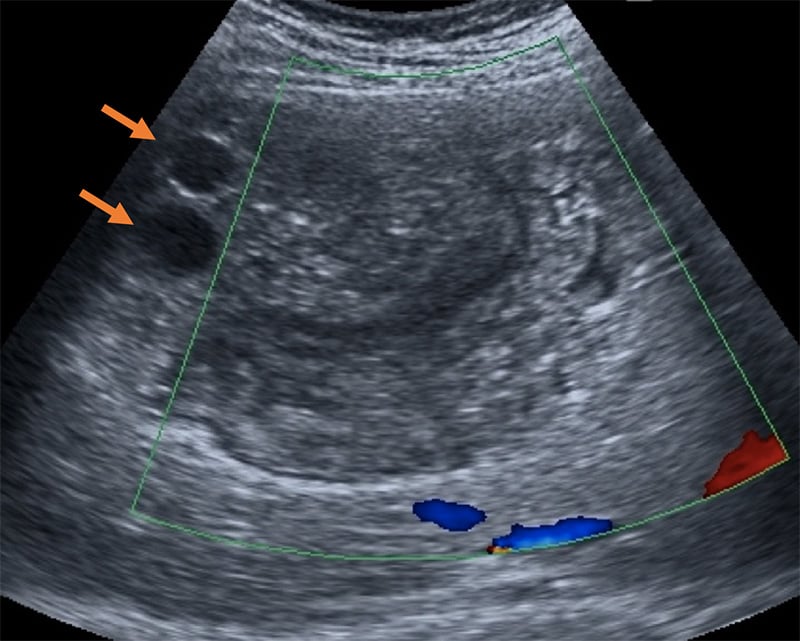

Figure 48. Ultrasonography images of urinary bladder of [School-Aged Children] infected with S. haematobium. a) Thickening of the bladder wall, transverse plane shows thickening of the left lateral wall (arrows); b) Diffuse thickening of the bladder wall more evident in the right posterior wall, echogenic snow in the lumen; c) In oblique longitudinal plane, ultrasound image shows a mass-like lesion in the mucosa layer of the bladder. Block arrow indicates the dilation of the ureter; d) longitudinal plane shows a marked and diffuse thickening of the bladder wall with a mass-like lesion (arrow); e) Mass-like lesion in the absence of a marked and diffuse thickening of the bladder wall; f) Multifocal thickening of the wall, particularly evident on the right and posterior wall. (Reproduced with permission, PLOS https://doi.org/10.1371/journal.pntd.0005400.g003 )